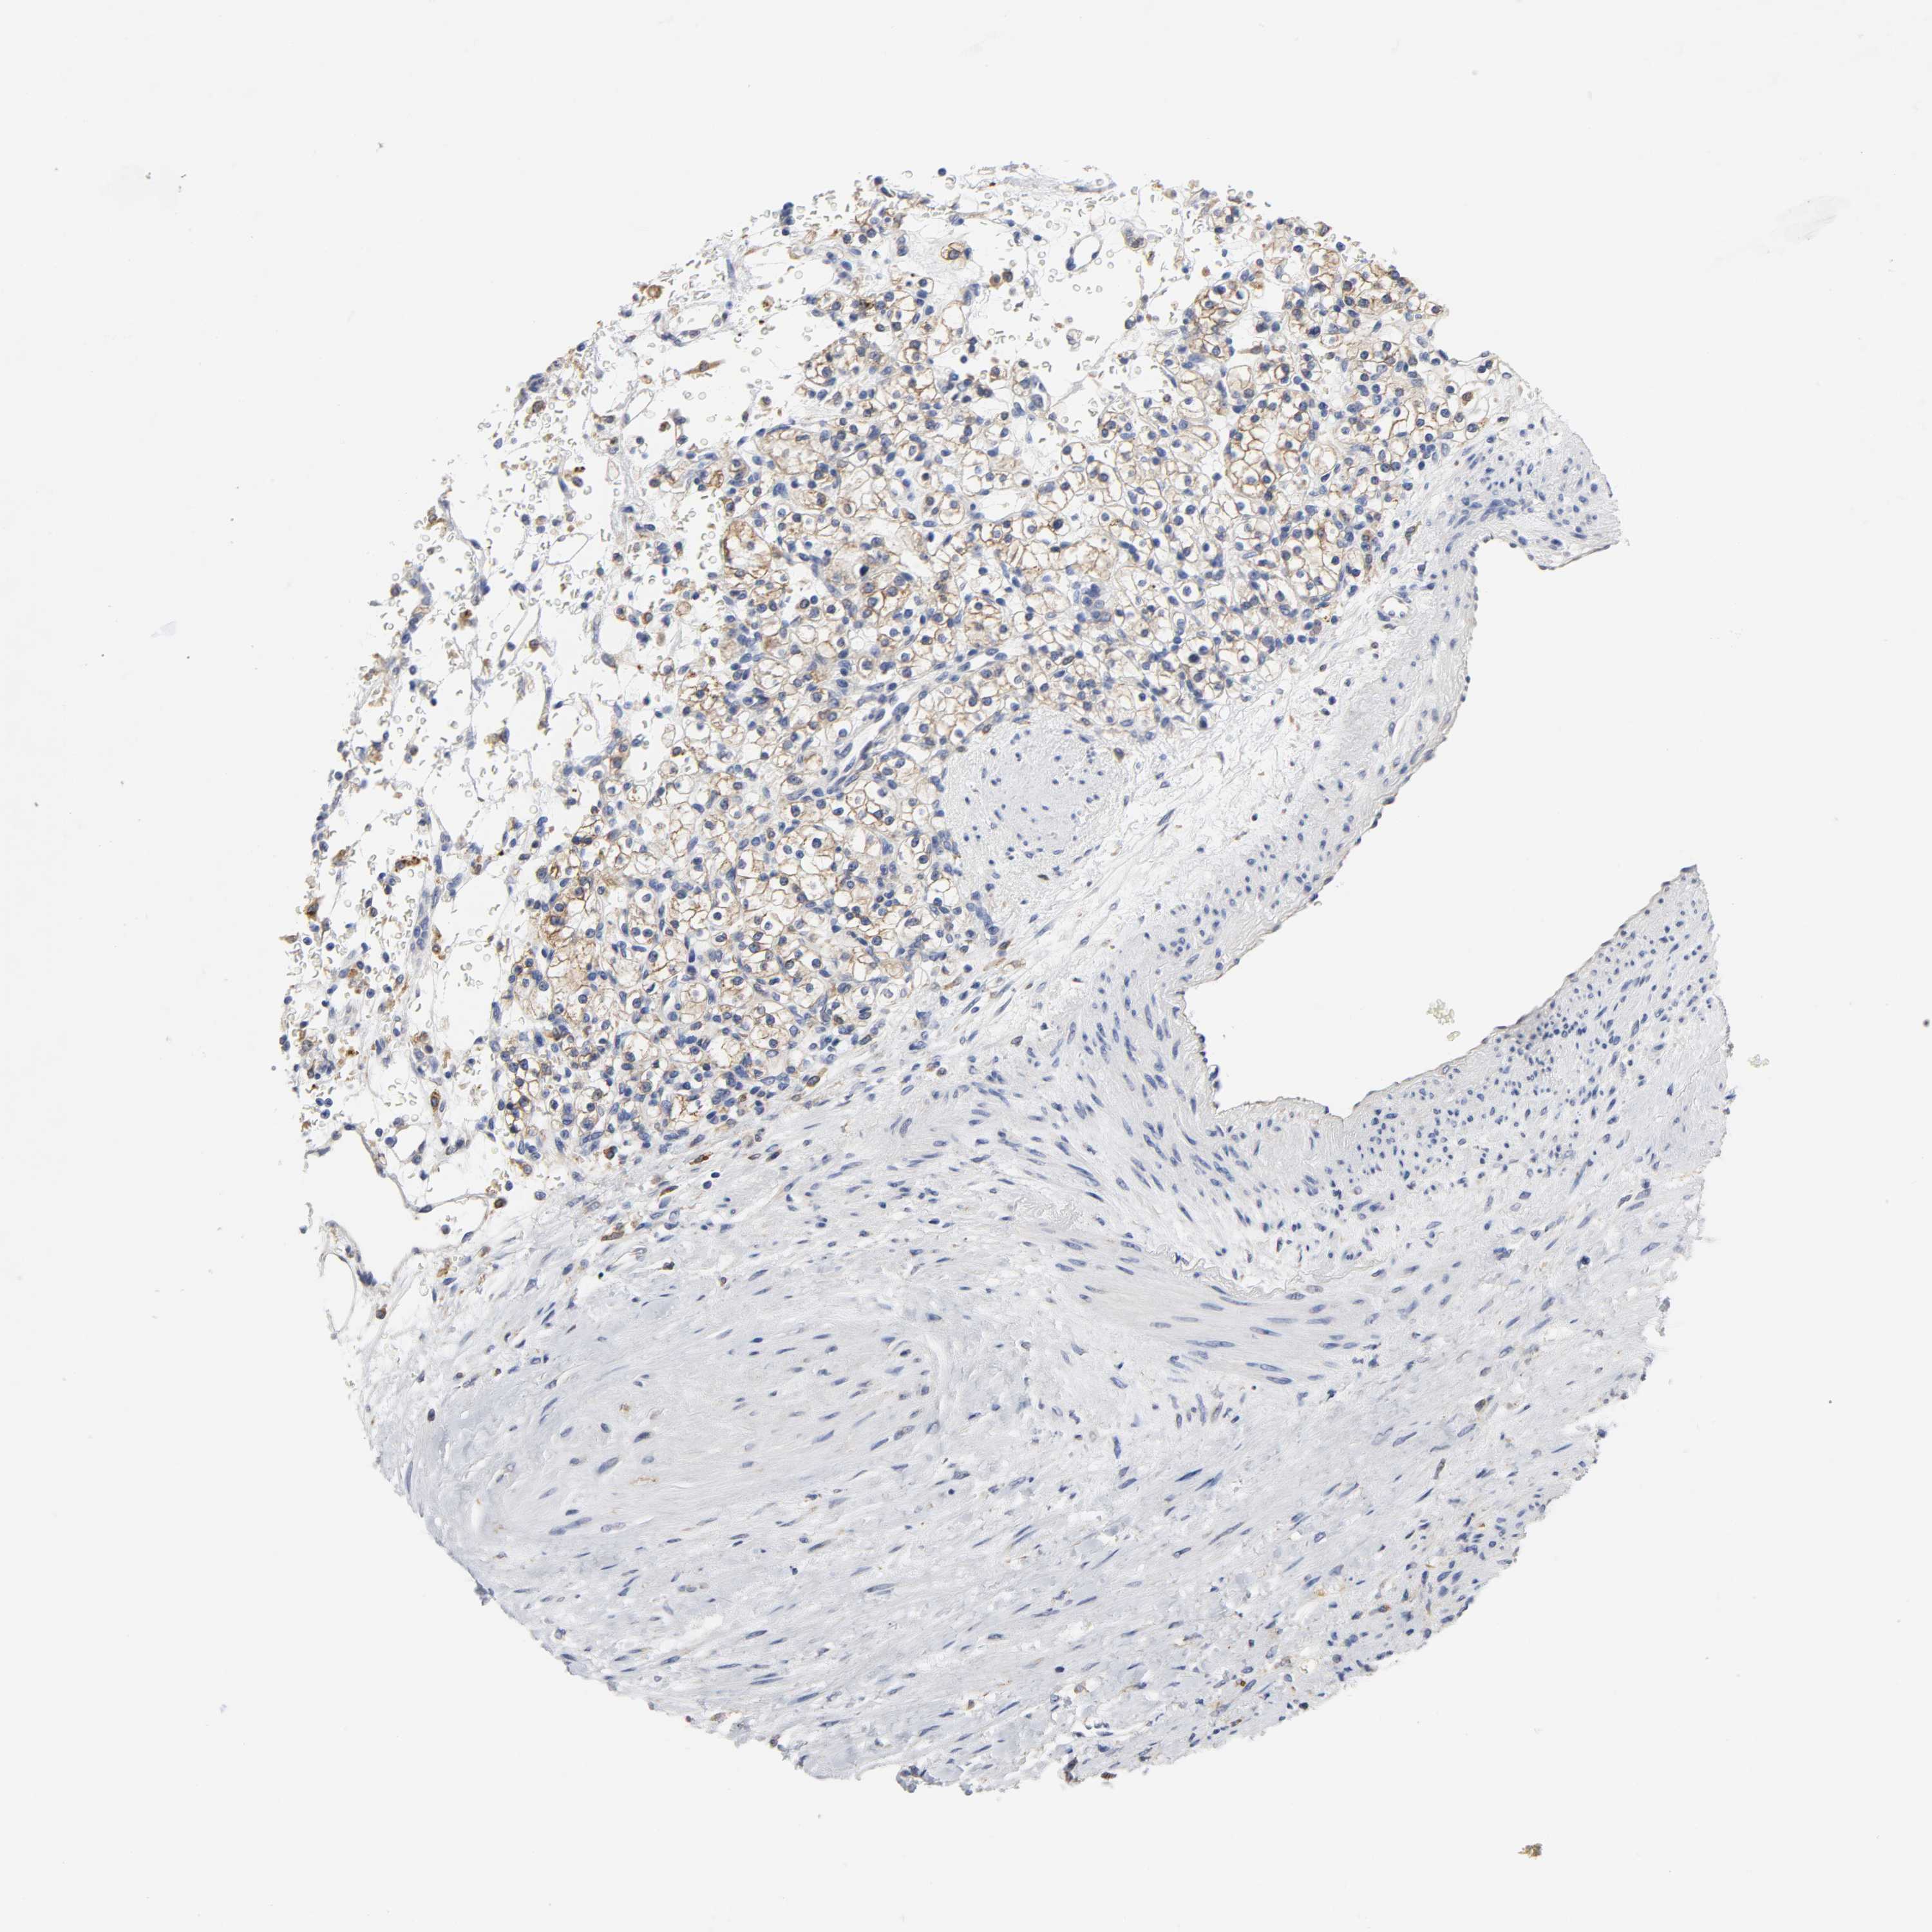

KIDNEY RENAL PAPILLARY CELL CARCINOMA (TCGA) - Interactive survival scatter ploti

The Survival Scatter plot shows the clinical status (i.e. dead or alive) for all individuals in the patient cohort, based on the same data that underlies the corresponding Kaplan-Meier plots. Patients that are alive at last time for follow-up are shown in blue and patients who have died during the study are shown in red.

HCK is not prognostic in Kidney Renal Papillary Cell Carcinoma (TCGA)

Best expression cut offi

Based on the FPKM value of each gene, patients were classified into two groups and association between prognosis (survival) and gene expression (FPKM) was examined. The best expression cut-off refers the FPKM value that yields maximal difference with regard to survival between the two groups at the lowest log-rank P-value. Best expression cut-off was selected based on survival analysis .

When clicking on this number, the vertical dashed line indicating cut-off, the interactive survival plot, and the Kaplan-Meier curve will be adjusted to show results based on the best expression cut-off.

: 3.57